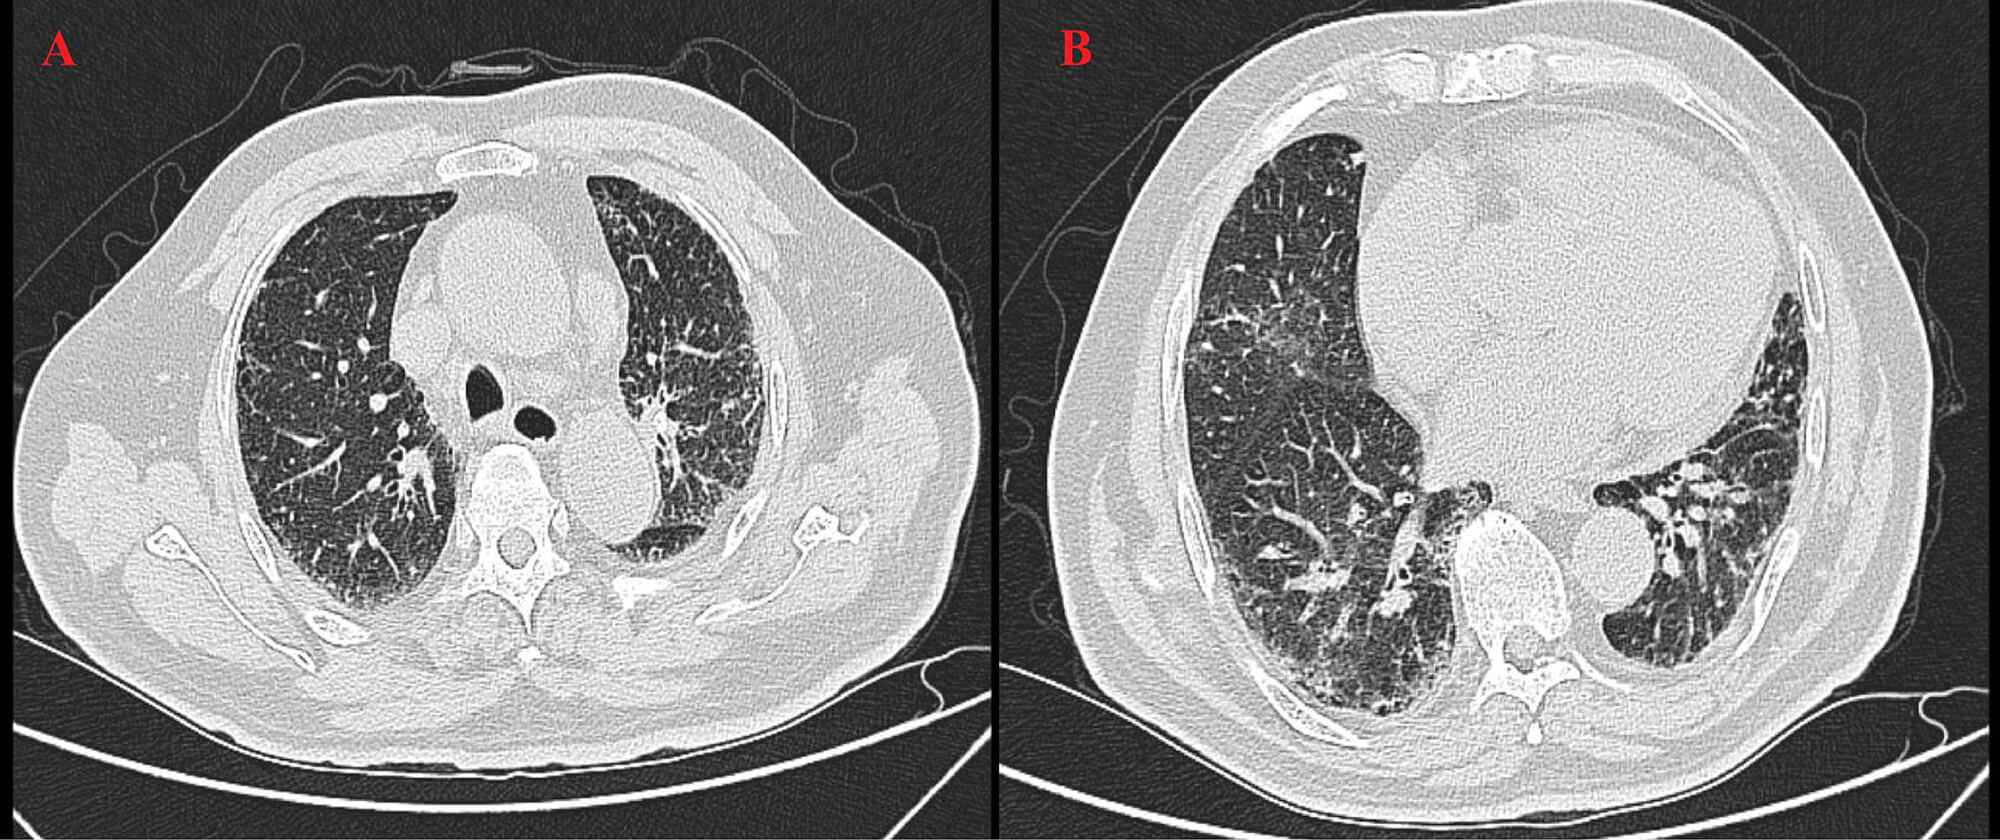

High-resolution computed tomography (HRCT) (Fig. 3) revealed patchy opacities in the left upper and right lower lobes, accompanied by multiple enlarged hilar and mediastinal lymph nodes (Fig. 4), interstitial inflammation in both lungs (Fig. 5), and a small pleural effusion. These findings were consistent with residual tumor and local progression following treatment for extensive-stage SCLC, demonstrating characteristic imaging features of SCLC.

Fig. 5.

HRCT on 22 August 2025. (A) The left upper lobe shows fibrotic changes and partial absorption, indicating post-treatment improvement. (B) The right lower lobe shows persistent high-density areas and mild pleural effusion, indicating residual inflammation and need for follow-up.